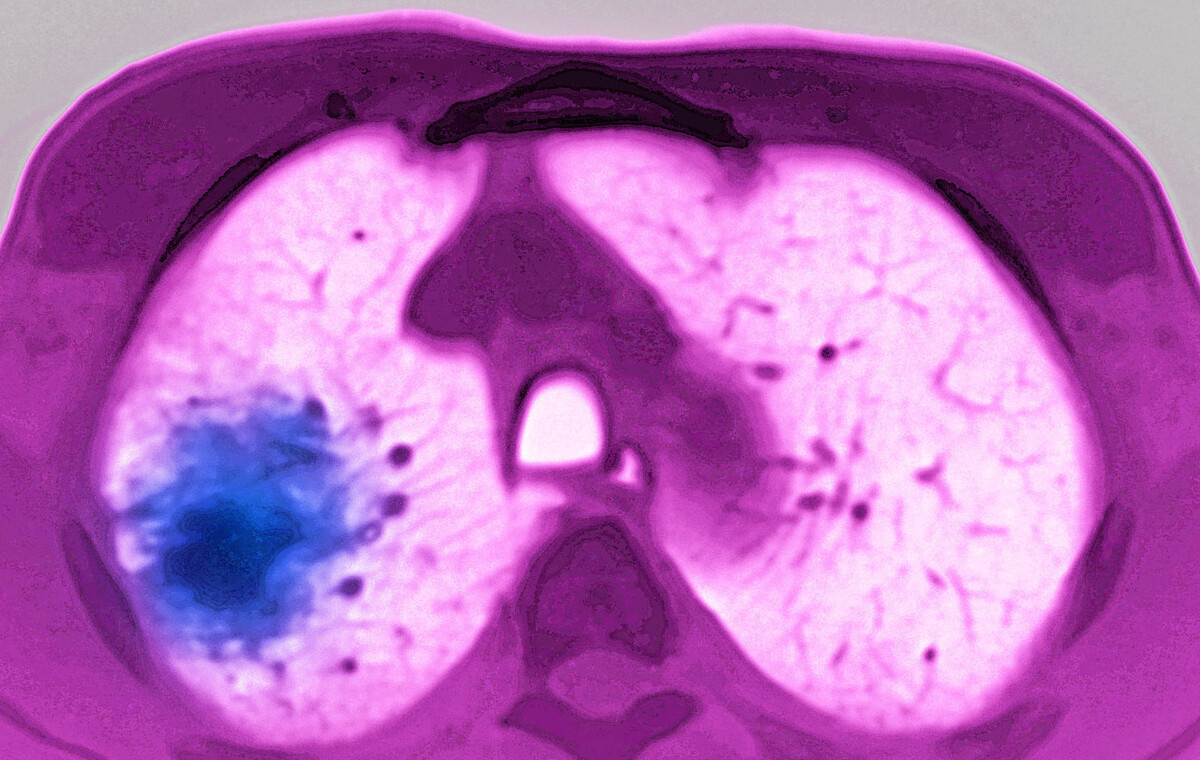

吴阿姨是个小细胞肺癌患者 , 病灶在左下肺 , 纵隔淋巴结有转移 , 只能选择化疗联合免疫治疗 。 治疗前 , 吴阿姨整天觉得乏力 , 胃口也不好 , 时常有低热和咳嗽 。 治疗两周期后 , 吴阿姨觉得好像咳嗽减少了 , 乏力感也减轻了 。 来门诊复查时听了她的描述 , 我认定她的病灶一定缩小好转了 。 果然 , CT提示原来肿大的纵隔淋巴结不见了 , 左下肺病灶也缩小了三分之二 。 听到这个消息 , 吴阿姨开心地回去等下一次治疗 。

在评估肺癌病情是否好转 , 最重要且有价值的检查 , 仍然是影像学检查 , 主要是CT、磁共振、PET-CT等等 , 前后对比 , 病灶是否好转一目了然 。 所以 , 对于带瘤的肺癌病人 , 一般治疗2-3周期后必须进行增强CT检查评估治疗效果 , 指导后续用药 。 病灶缩小 , 就意味着病情好转 。 不过在免疫治疗时代 , 也要警惕CT上的假性进展可能 。